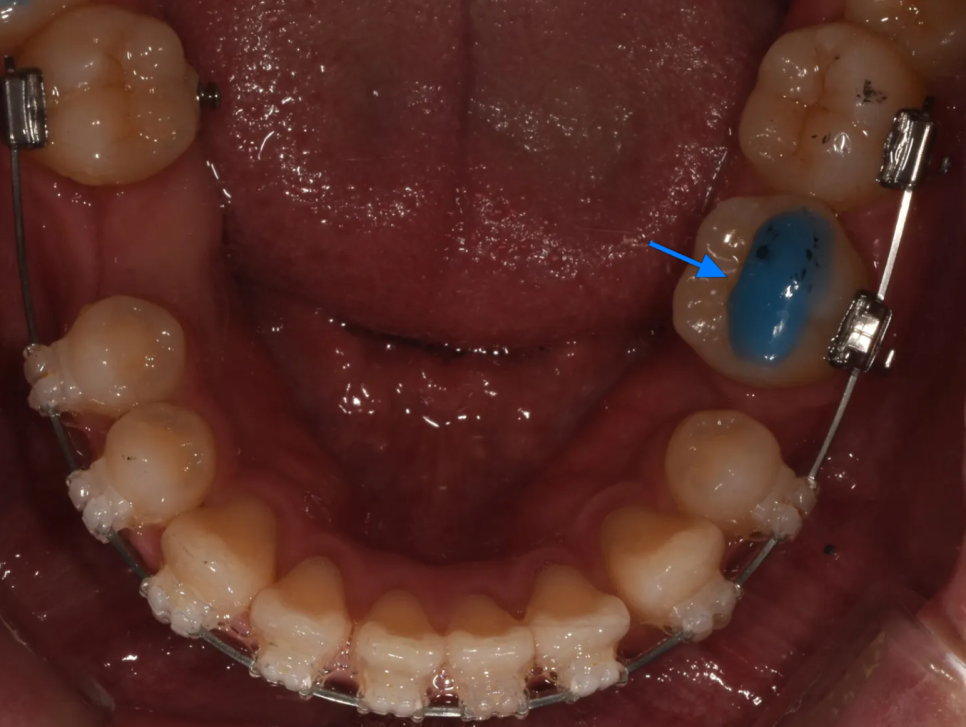

이때 한 가지 세심한 처치가 필요했습니다. 어금니를 안쪽으로 움직이는 과정에서 아랫니와 간섭(부딪힘)이 생길 수 있기때문에, 반대쪽 치아에 '바이트 플레인(bite plane)'이라는 장치를 만들어주었습니다.

바이트 플레인이란?

치아 위에 붙이는 플라스틱 블록으로, 특정 치아끼리 닿지 않도록 교합 높이를 일시적으로 올려주는 장치입니다

반대쪽에 바이트 플레인을 만들어 일시적으로 끝까지 못 물게 해줘, 교합 간섭을 방지합니다